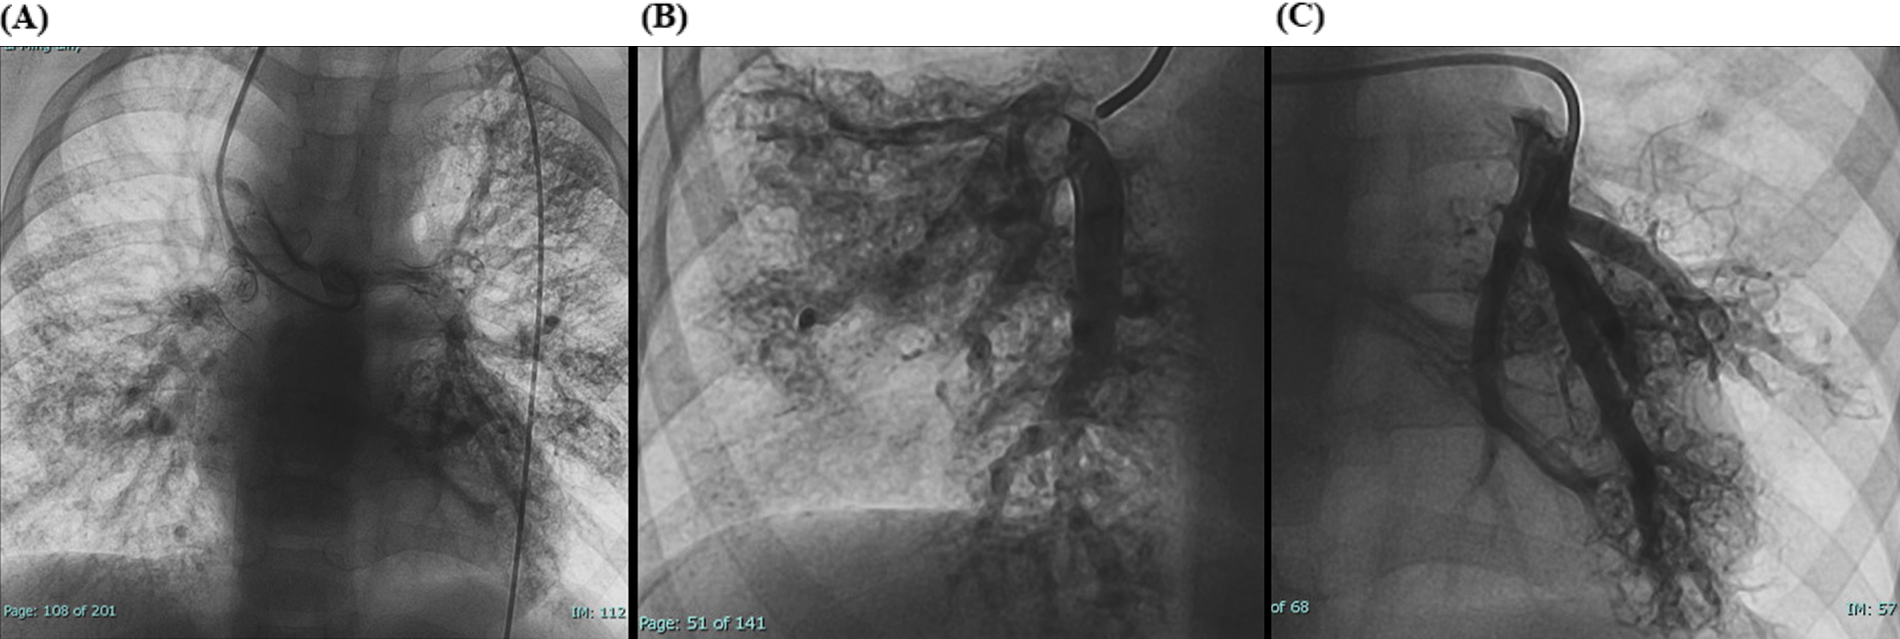

Laboratory tests showed hemoglobin of 225 g/L and hematocrit of 73.3%. Arterial blood gas analysis revealed a partial pressure of oxygen (PO₂) of 30.7 mmHg and oxygen saturation (SO₂) of 58.1%. Chest X-ray showed cardiomegaly (cardiothoracic ratio 0.6) and increased pulmonary markings (Figure 1A). Echocardiography revealed absence of antegrade pulmonary artery flow; a 23 mm VSD located beneath the pulmonary valve with bidirectional shunting; a 23 mm ASD with bidirectional shunt; and a patent Glenn anastomosis. Contrast-enhanced CT showed ASD and VSD, absence of the pulmonary valve and main pulmonary artery, confluence of the right and left pulmonary arteries, reduced pulmonary blood flow, and extensive PAVMs in both lungs—most prominent in the lower lobes (Figure 1B). The measured McGoon ratio was 1.857. Cardiac catheterization confirmed absence of antegrade pulmonary artery flow, with well-developed right and left pulmonary arteries. The distal pulmonary arteries and pulmonary venous branches were markedly dilated, with some showing a granular or “string-of-beads” appearance (Figure 2). Pulmonary circulation time was significantly shortened, indicating substantial right-to-left intrapulmonary shunting, consistent with diffuse PAVMs. The lower lobes were most severely involved. Pulmonary artery pressure was 17/9/13 mmHg.

Figure 2

(A) Preoperative cardiac catheterization showing diffuse bilateral pulmonary arteriovenous malformations (PAVMs). (B,C) Local cardiac catheterization angiographic views showing PAVMs more pronounced in the lower lobes.